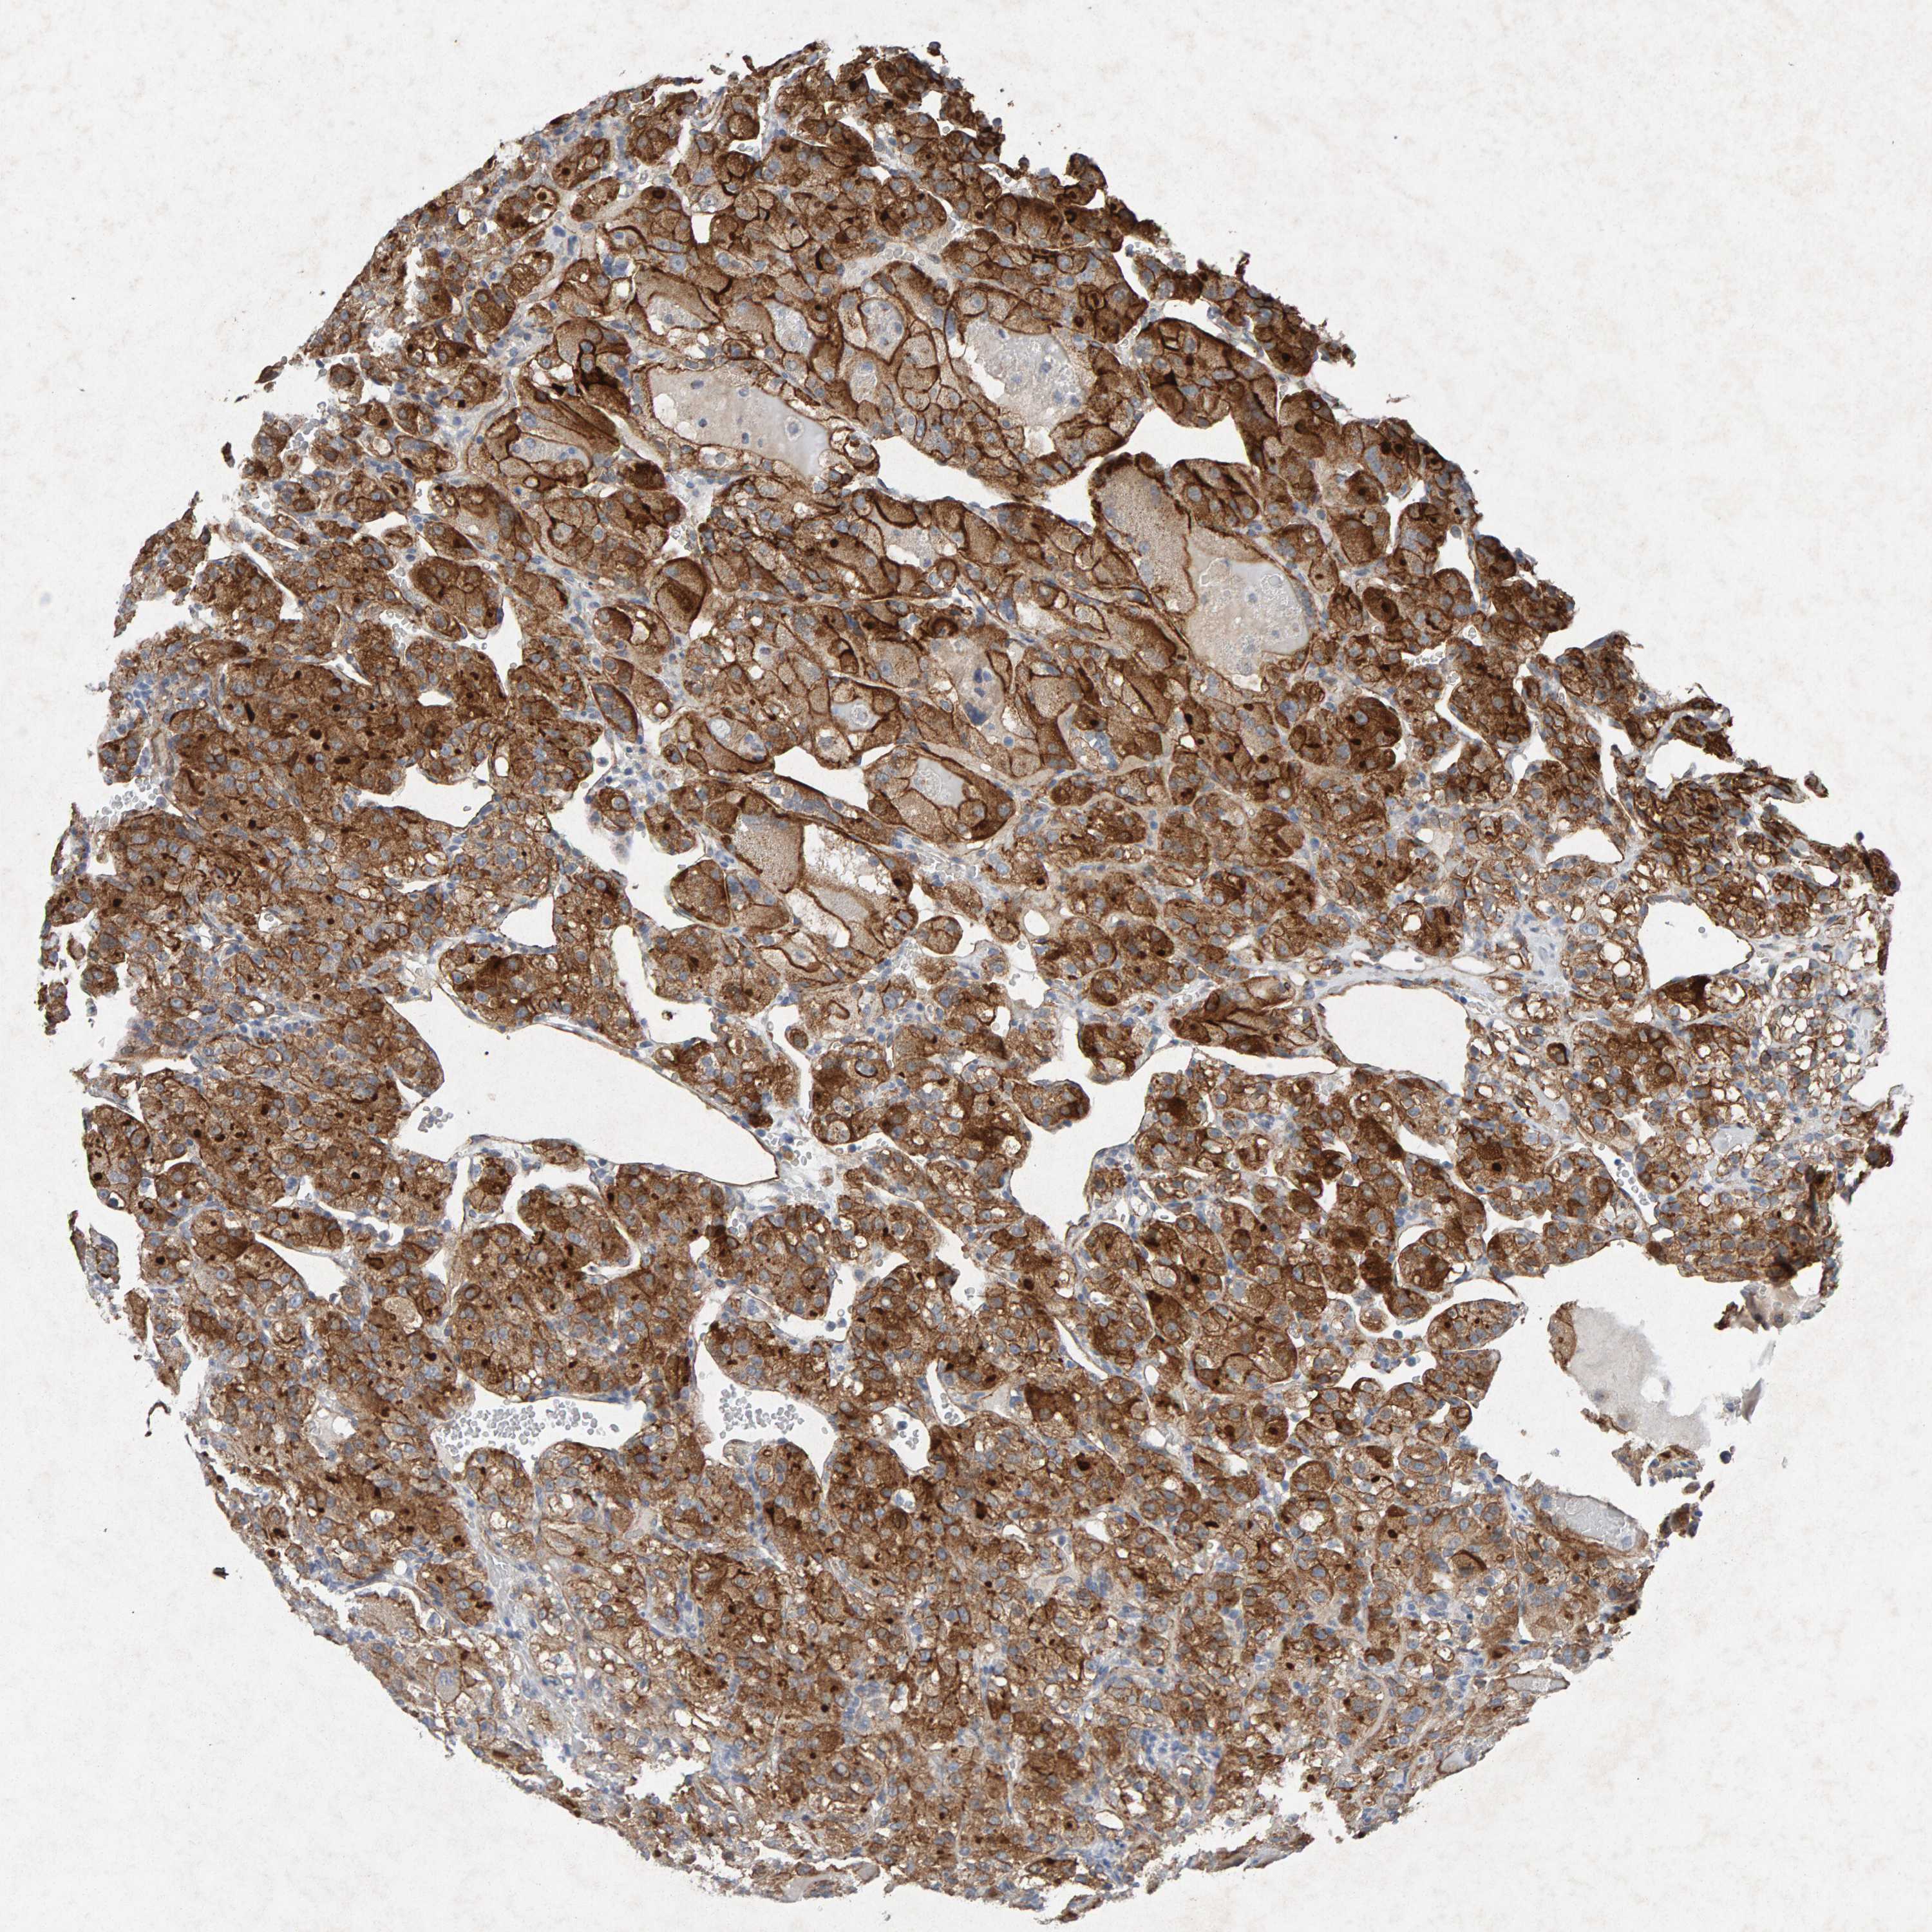

PTPRM is validated prognostic, high expression is favorable in Kidney Renal Clear Cell Carcinoma (TCGA)

Stage:

Survival analysis

Best expression cut offi

Based on the FPKM value of each gene, patients were classified into two groups and association between prognosis (survival) and gene expression (FPKM) was examined. The best expression cut-off refers the FPKM value that yields maximal difference with regard to survival between the two groups at the lowest log-rank P-value. Best expression cut-off was selected based on survival analysis .

When clicking on this number, the vertical dashed line indicating cut-off, the interactive survival plot, and the Kaplan-Meier curve will be adjusted to show results based on the best expression cut-off.

: 47.24

Average pTPM 54.6

Number of samples 521